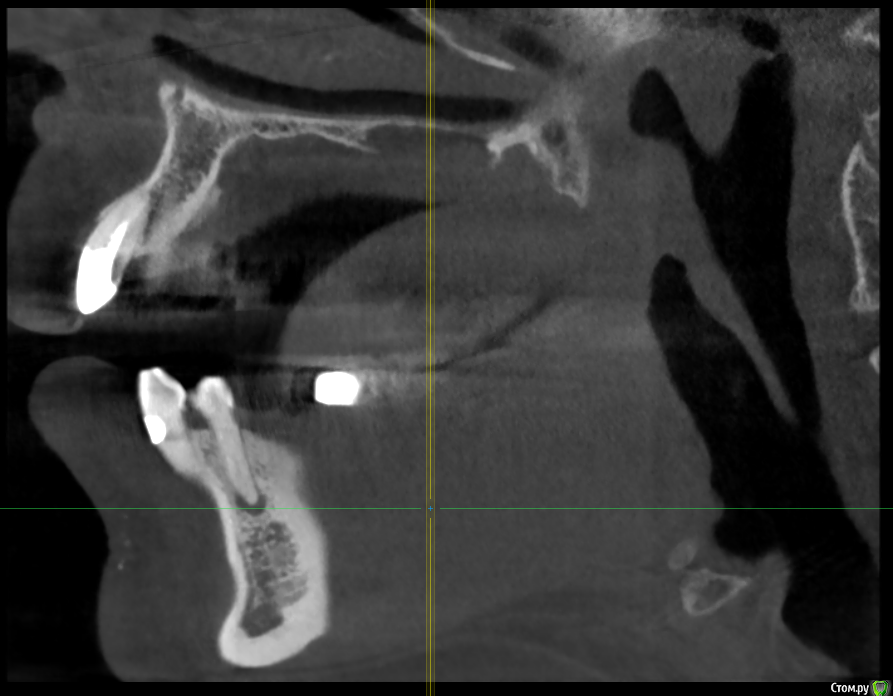

Patrick Опубликовано 18 апреля, 2019 Поделиться Опубликовано 18 апреля, 2019 Добрый день, есть ли шанс вылечить этот зуб? Или смело (насколько возможно) удалять?(Неделю назад удалили соседний зуб, а сейчас и этот стал ныть) Спасибо! Ссылка на комментарий

krokomot Опубликовано 18 апреля, 2019 Поделиться Опубликовано 18 апреля, 2019 если вы про нижний зуб с кистозным образованием, то требуется лечение каналов этого зуба, и все будет хорошо. 2 Ссылка на комментарий